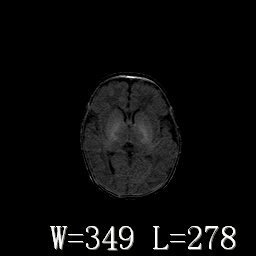

男,4天,发复抽搐1天。

hie?

脑干形态欠规则,信号增高,不知怎么解释?